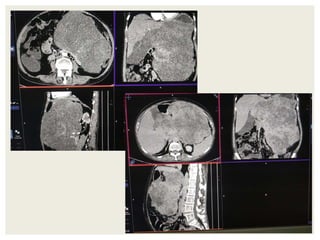

CASE2

DIFFERENTIALS

Diagnosis Points in favour Points against

Retroperitoneal

sarcomas

• Leiomyosarcoma

/Undifferentiated

Liposarcoma

• MFH

Age and clinical

presentation

Imaging features

(Large ill defined

heterogeneously

enhancing lesion

with areas of

necrosis)

No fat density/

calcification

No calcification

GIST Age

Biopsy:

 Poorly differentiated Leiomyosarcoma